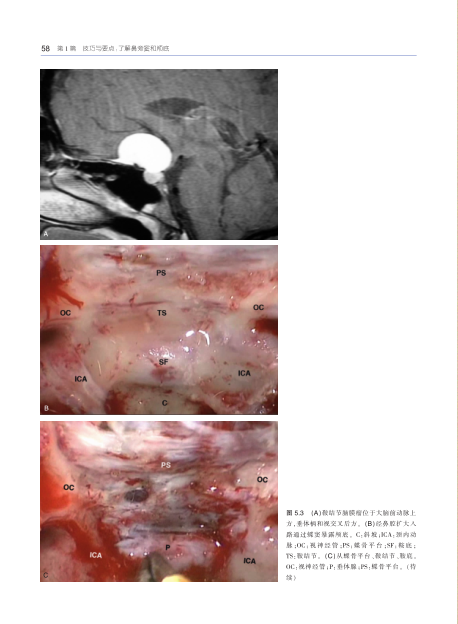

经鼻内镜颅底和脑外科手术学技巧与要点 微创神经外科 鼻腔鼻旁窦 内镜下经鼻开颅术 耳鼻喉科头颈外科医师参考书 解剖 正版